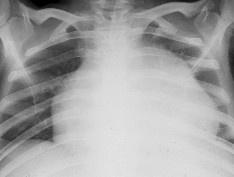

• 限制型心肌病

628健康網(wǎng)為您分享有關(guān)限制型心肌病的癥狀,限制型心肌病的治療方法,限制型心肌病的預(yù)防知識,限制型心肌病的癥狀圖片,限...